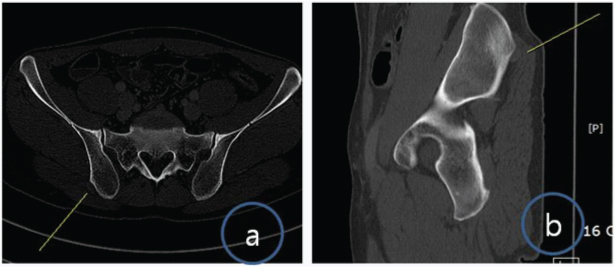

A 34-year-old man presented with pain in posterior pelvis near the right sacroiliac joint for last three months. Although there was no visible swelling but a small tender swelling felt on deep palpation. It was pea-sized and fixed. The surrounding skin was normal. There was no other swelling, café-au-lait spot or cutaneous neurofibroma. He had no significant past medical or family history. There were no other constitutional symptoms such as low grade fever, chills, or weight loss. Anteroposterior pelvic radiograph showed an ill-defined lytic lesion with non-sclerotic margins near inferior aspect of right sacroiliac joint. There was no sub-periosteal reaction or new bone formation [Table/Fig-1]. CT scan pelvis showed two small nodular soft tissue density lesions near right posterior iliac wing (about 1.1 cm in size) with osseous pressure erosion [Table/Fig-2a,b].

(a) Transverse CT scan demonstrates small nodular soft tissue density lesion near right posterior iliac wing with slight osseous pressure erosion; (b) Sagittal CT scan demonstrates small nodular soft tissue density lesion near right posterior iliac wing.